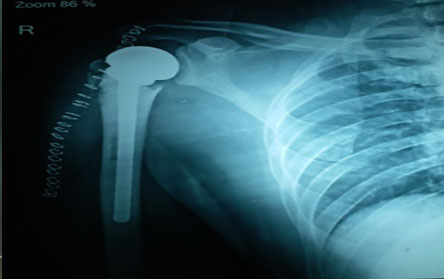

Trauma surgery:

Trauma surgery is a surgical specialty that utilizes both operative and non-operative management to treat traumatic injuries.

The Center of Orthopedics KUMAR ORTHO HOSPITAL ,Patna, offers the entire spectrum of modern orthopedic management, which is effective, patient - friendly & result oriented. In a nutshell, it is one stop treatment for all orthopedic ailments and fractures with emphasis on avoidance of complications, rapid mobilization, decreased period of confinement and an early return to normalcy.